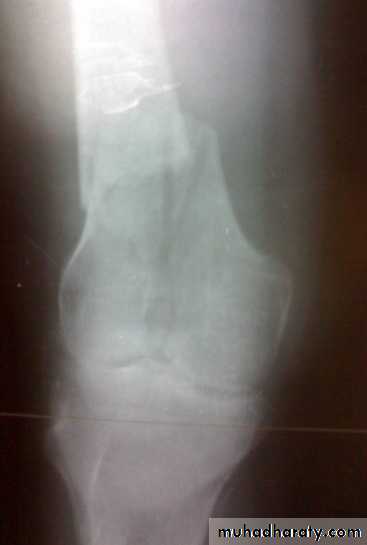

Tibial plateau fractures

Mechanism: medial or lateral bending force with axial loads, e.g. bumper fracture.

Doughy swelling of hemarthrosis.

Diffuse tenderness.

May be associated with knee ligament injury (collateral ligament, cruciate ligament).

X-ray:

One or both condyles may fracture with varying degrees of comminution.

Treatment

Aspirate hemarthrosis.Minimally displaced fractures: compression bandage, gradual exercise,then functional brace and gradual exercise after 3 wks.

Displaced and/ or comminuted lateral or medial tibial condyle fracture

Treatment:ORIF.

Associated ligament injury repaired.

Bicondylar fracture: needs ORIF with plate and screws or external fixation.